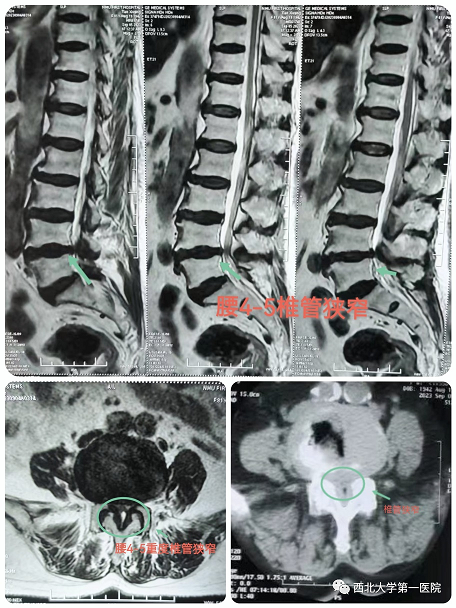

患者田某某,女,81岁,有腰腿痛病史10余年,近期出现左下肢放射痛,不能长距离行走,辗转多家医院保守治疗,效果不佳,行走困难,严重影响日常生活和休息,为求诊治,来六合彩生肖骨科三病区。六合彩生肖 脊柱外科团队经过细致的体格检查及辅助检查,明确诊断:腰4-5椎管狭窄症。患者症状体征与检查结果相符,重度椎管狭窄,继续保守治疗可能没有效果。患者高龄,81岁,基础病较多,开放手术风险较高,患者及家属不能接受,与患者及家属充分沟通后,建议可以考虑微创椎管减压术,在取得患者家属的理解后,同意行微创手术治疗。

经过充分的术前讨论及围手术期多学科讨论评估后,决定采用目前最新脊柱内镜技术:OSE(Open Spine Endoscope)单孔脊柱内镜技术,行腰4-5椎管狭窄单侧入路、双侧减压、脊神经根粘连松解术。手术切口约2cm,术中出血10ml左右,由于不破坏关节突关节,不影响脊柱稳定性。术后第二天患者佩戴腰带下地活动,症状明显缓解,效果非常满意。

术中可见椎管减压彻底,神经根完全松解